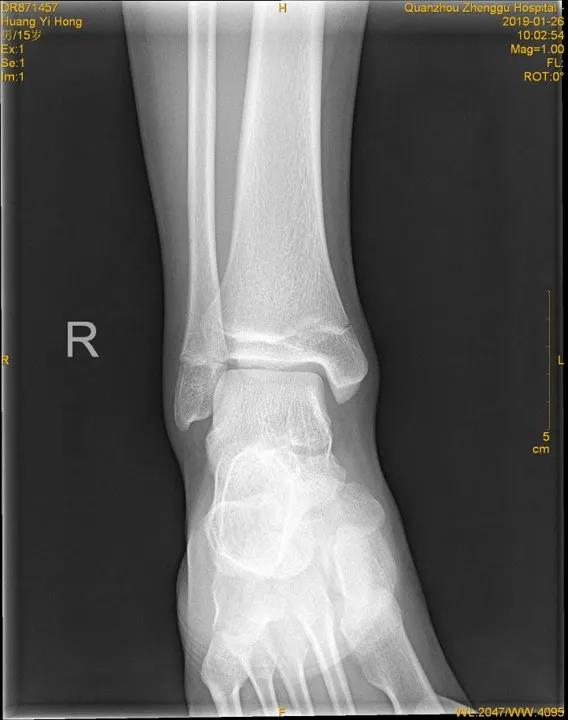

X线

踝关节正位

儿童骨骺未闭